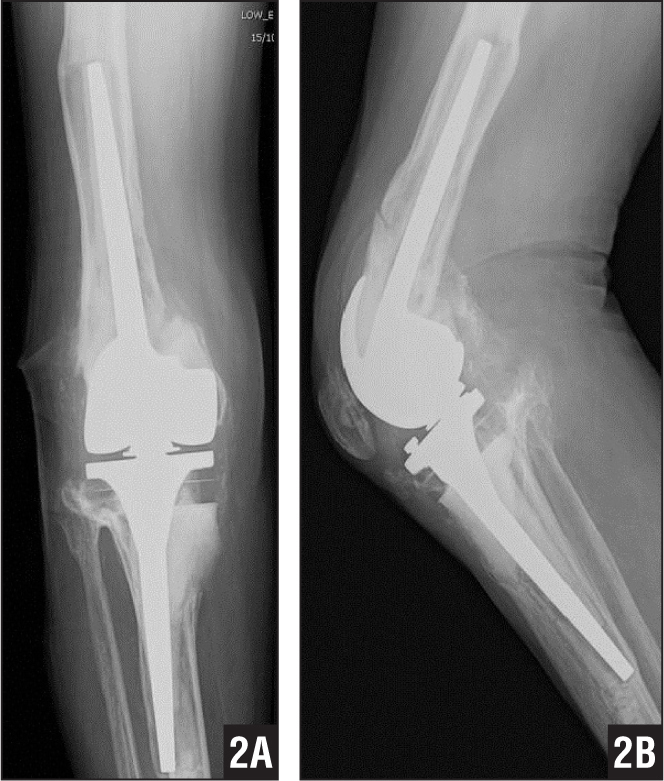

Indications for the use of this prosthesis?

the patient depicted had instability following CR knee and PCL rupture